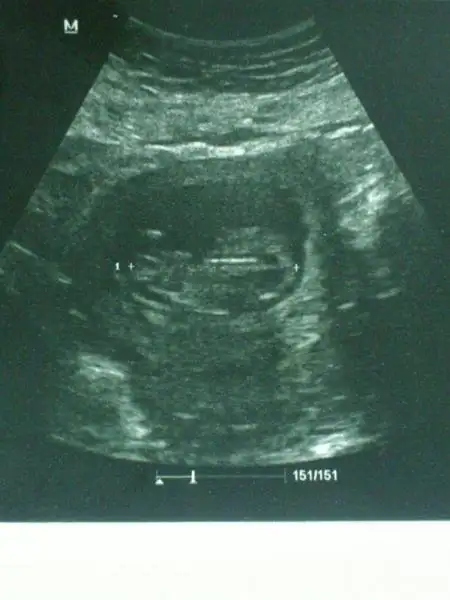

Eki Görüntüle 950359 Eki Görüntüle 950359 bnmki ne sizce

Eki Görüntüle 949203 bu daha net ise yorum alabilirmiyim lütfen? şimdiden teşekkürler

Bu da benim fistikkkkk....yuklendimi bilmiyorum..bence kiz.....sizce??? Dr tahmin soylemedi subat sonu gidicem artik o zaman oyrenirim kesin.ama bence kiz![]()

kiz ihtimali yuksek

erkekk guzelimmm buuuu

kizzzzzz oabuluuuu

Tahminde bulunabilecek kadar olmuş mu 10+3 ?Eki Görüntüle 953233 Eki Görüntüle 953232 Eki Görüntüle 953234